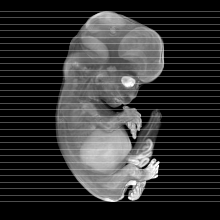

Carnegie Stage 22 (54 post-ovulatory days)

Most embryos at stage 22 are approximately 54 postovulatory days old and measure 25-27 mm in length. Distinguishing criteria for this stage include clear formation of the external ear, the hands begin to extend ventrally beyond the body wall, the fingers of one hand may overlap the fingers of the opposite hand, thickened eyelids just begin to cover the outer margins of the eye, and the superficial vascular plexus of the head now extends about three-quarters of the way above the eye-ear level.